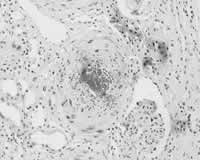

入院当日,患者尿量1750 mk,尿沉渣镜检:红细胞8~10 个/高倍视野,正常形态100 %;24 h尿蛋白定量0.39 g(参考值:<0.15 g)。予甲泼尼龙1 g/d×3日静点,继以泼尼松60 mg/d口服。冲击治疗次日,患者腹痛缓解,但尿量仅300 mk,血钾6.78 mmok/L,遂行血液透析。冲击治疗结束当日,患者无诱因再次出现腹痛,尿色呈洗肉水样,体温最高39.2 ℃。腹痛为上腹部两侧持续性绞窄性剧烈疼痛,无放射,不伴尿急、尿痛、呕吐、腹泻。查体:腹膜刺激征阴性,肠鸣音存在,双肾区叩痛阳性。实验室检查:血小板(PLT)计数下降,(116×109 /L→47×109 /L);激活的部分凝血活酶时间(APTT)58.4 s(参考值:28~42 s);血浆鱼精蛋白副凝试验阴性(参考值:阴性),优球蛋白溶解时间>90 s(参考值:<90 s)。腹部平片和B超未见异常;双肾动、静脉及肠系膜上动脉彩超未见异常。因观察到患者腹痛在血液透析开始后1 h左右明显减轻,而在血液透析结束后数小时又加重,故推测腹痛减轻与血液透析中应用肝素有关,遂于5月1日起予低分子肝素钙(速避凝)0.1 mg/d皮下注射。抗凝治疗2天后,患者腹痛缓解,体温正常,血小板计数、APTT逐渐恢复正常。住院期间,相隔8周两次查狼疮抗凝物(LA)阳性(参考值:阴性),抗心磷脂抗体(ACL)阴性(参考值:阴性)。5月30日,在全麻下行开放性肾活检术,病理结果:光镜下可见肾小动脉多数血栓形成,内膜呈葱皮样增厚,管腔狭窄及闭塞,多数肾小球呈缺血性皱缩,部分呈缺血性硬化;免疫荧光全部阴性(图1,图2)。住院期间,患者肾功能无恢复,予泼尼松60 mg/d 12周后逐渐减量),2001年8月出院。

图2 肾小动脉血栓形成,内膜呈葱皮样增厚,管腔严重狭窄。(PAS-M染色,×200)

APS可累及多系统,肾脏是APS的主要靶器官之一。APS的肾脏病理改变主要为肾血管血栓形成,从肾血管主干到肾小球毛细血管的各级血管均可受累,以血栓性微血管病(TMA)最为典型。光镜下,TMA在急性期可表现为内皮细胞肿胀、变性,血管壁纤维素样坏死,血管腔内血栓形成;在慢性期则可见血管壁增生性改变,血栓部分再通等。免疫荧光检查应无免疫复合物沉积。APS的肾脏损害在临床上可表现为不同程度的蛋白尿、高血压、肾功能损害,严重者可致急性肾衰,当发生肾梗死时可表现为腰痛、腹痛、肉眼血尿等。APS所致肾脏TMA是本例急性肾衰的原因。